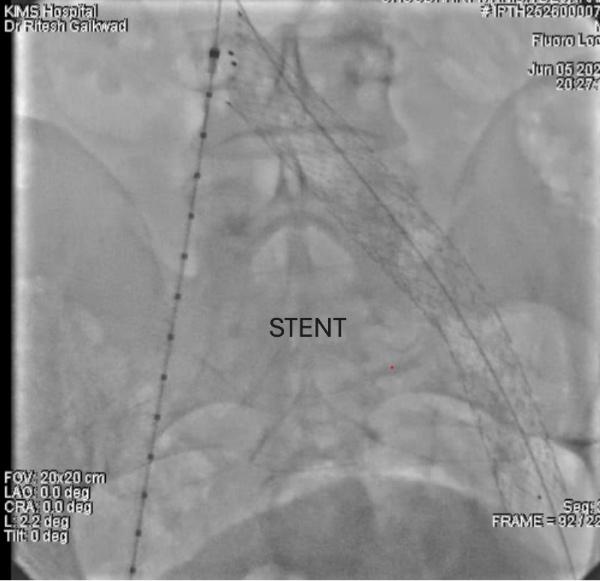

The patient underwent balloon angioplasty followed by deployment of a dedicated self-expanding venous stent in the compressed segment of the left iliac vein. The procedure was uneventful, completed in under an hour, and the patient was mobilized within two hours postoperatively.

More importantly, treating the root cause with iliac vein stenting, particularly using modern, dedicated venous stents, offers excellent results. These stents are designed to handle the dynamic, compressive environment of the pelvis and provide long-term patency with minimal complications.